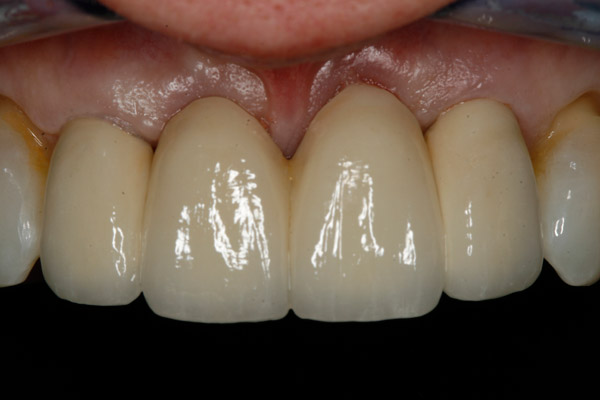

Thank you to our patients that have allowed us to show examples of our work

Have a look at just some of the many patient examples we have captured from BEFORE and AFTER their treatments and cosmetic surgeries.

From Whitening to Veneers, Fillings to Cosmetic Teeth Makeovers, here are some examples of the work that Dr. Dadabhai has provided to his patients to give them a more confident smile and a positive, pain free feeling.

Much of the work we carry out is to relieve pain and of course maintain the health of your teeth and gums, but many of our patients now ask for Cosmetic work to give them a more confident smile.

Cosmetic support has improved hugely over the last few years. Book a Consultation with Dr Dadabhai and he will prescribe a course of treatment to complete your perfect SMILE transformation.

Slide your computer mouse or finger (touch screens) over the image to view BEFORE and AFTER comparison.